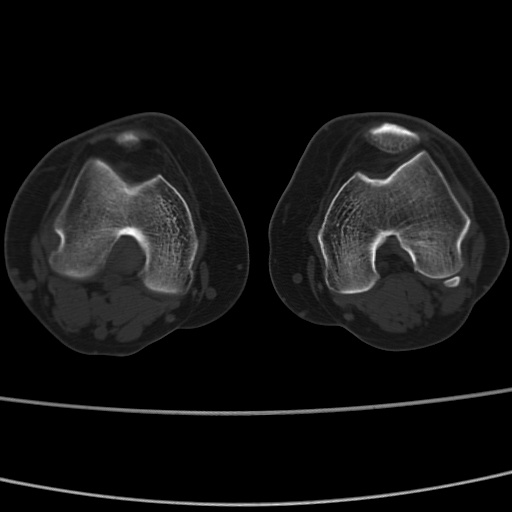

女性,50岁。【请提供患者临床症状体征】

胫骨后缘陈旧性骨折(是否有病史)

右膝关节退行性改变,关节游离鼠。

右膝关节退行性改变,滑膜黏液囊钙/骨化并游离。